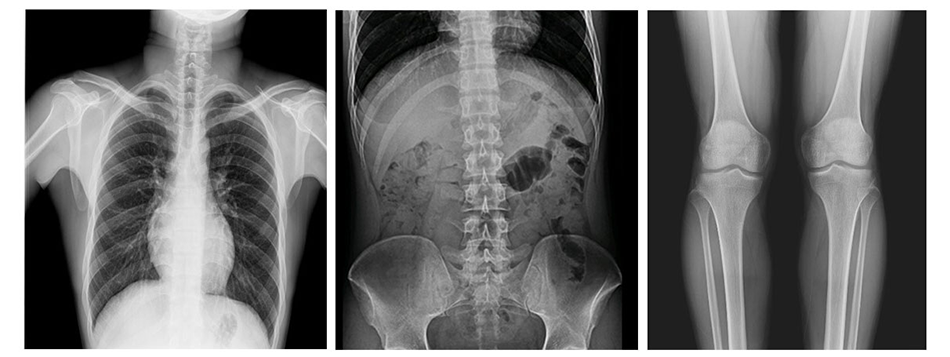

可供醫(yī)院對(duì)患者進(jìn)行人體頭部、頸部、胸部、腹部、腰椎、四肢等部位的臥位、正位、側(cè)位、斜位的X光攝影、透視及造影檢查。

5、自動(dòng)圖像拼接功能(選配)

應(yīng)用于全脊柱、全下肢的檢查,為臨床提供高精度的全景圖像。完全滿足醫(yī)院的骨科及矯形手術(shù)要求。